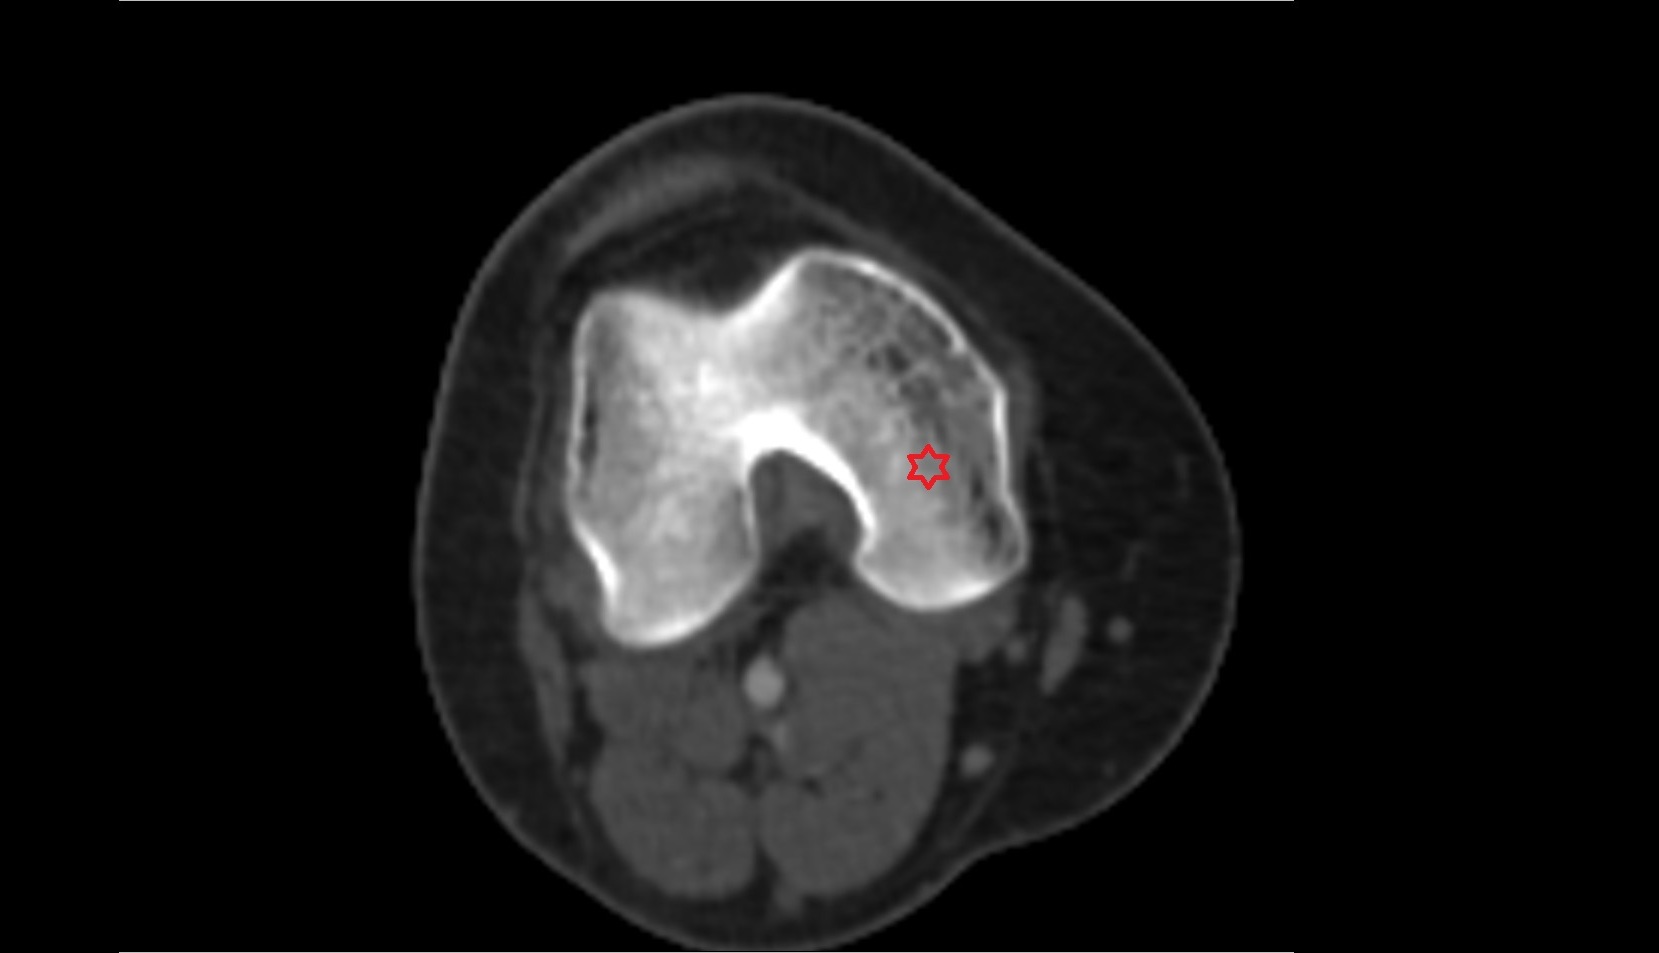

- Lateral condyle of femur

- Medial condyle of femur

- Medial epicondyle of femur

- Lateral epicondyle of femur

- Femoral condyle articular cartilage

- Knee Joint